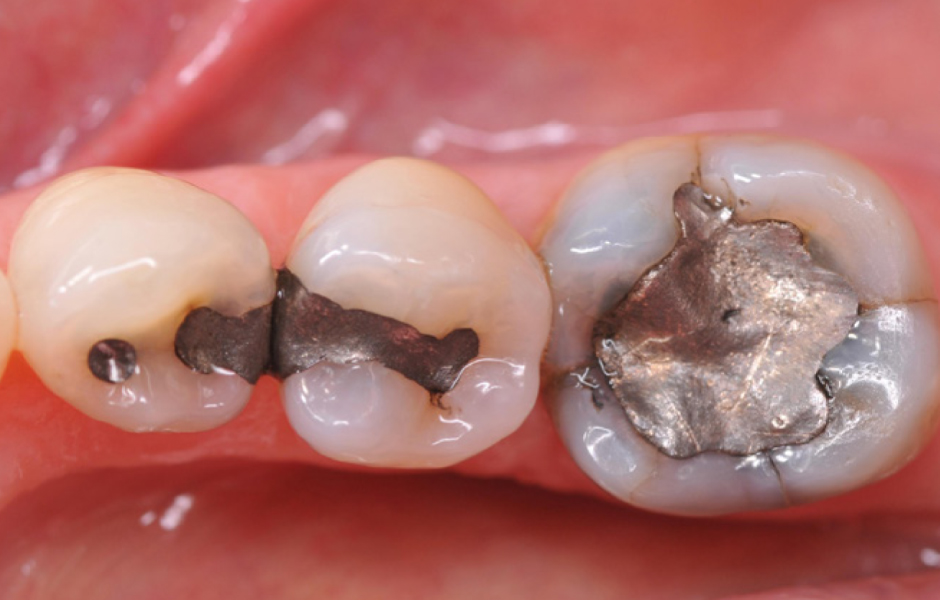

Obr. 1: Výchozí situace. Výchozí situace se týká staršího pacienta se starými amalgámovými výplněmi v pravém dolním distálním úseku, které si pacient přál odstranit z estetických důvodů.